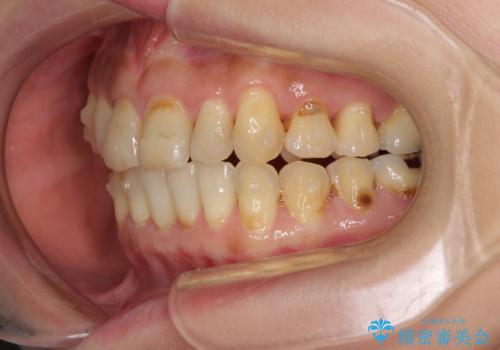

- 歯列不正と、どこで咬んで良いのか分からない咬み合わせを気にして来院された患者様です。

下顎骨は左側にシフトしており、咬み合ったときには奥歯と前歯の一部しか接触していない状態でした。

骨格的な左右差は歯列矯正は改善できないため、上下歯列が全体的に接触することをゴールとしてインビザラインにて矯正治療を行うこととしました。